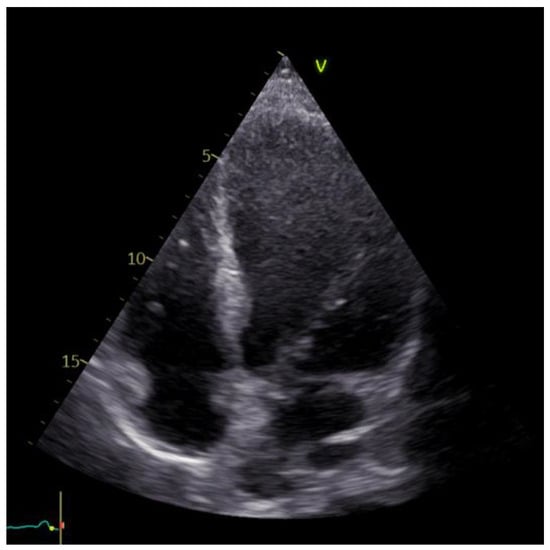

The echocardiographic examination identified a dilated left ventricle with hypokinesia observed in the anterolateral wall, apex, and interventricular septum; EF = 30%; moderate ischemic mitral regurgitation; mild tricuspid regurgitation; and no pericardial effusion. Furthermore, the investigation confirmed the apical left ventricle aneurysm (Figure 5).

Figure 5. Echocardiographic image of the left ventricle aneurysm.